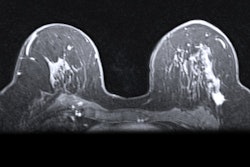

"Consequently, FDG-PET/MRI could be an all-in-one solution involving dedicated breast MRI and PET," Bruckmann told RSNA attendees. "Therefore, the purpose of our study was to evaluate the diagnostic accuracy of whole-body MRI to whole-body FDG-PET/MRI for the initial TNM staging for newly diagnosed histologically proven breast cancer patients."

For this prospective, multicenter study, the researchers included 104 consecutive women (mean age, 53.4 ± 12.5 years) with histologically proven breast cancer. All subjects underwent whole-body FDG-PET/MRI in the supine position from the head to the midthigh using a 3-tesla MRI and PET system.